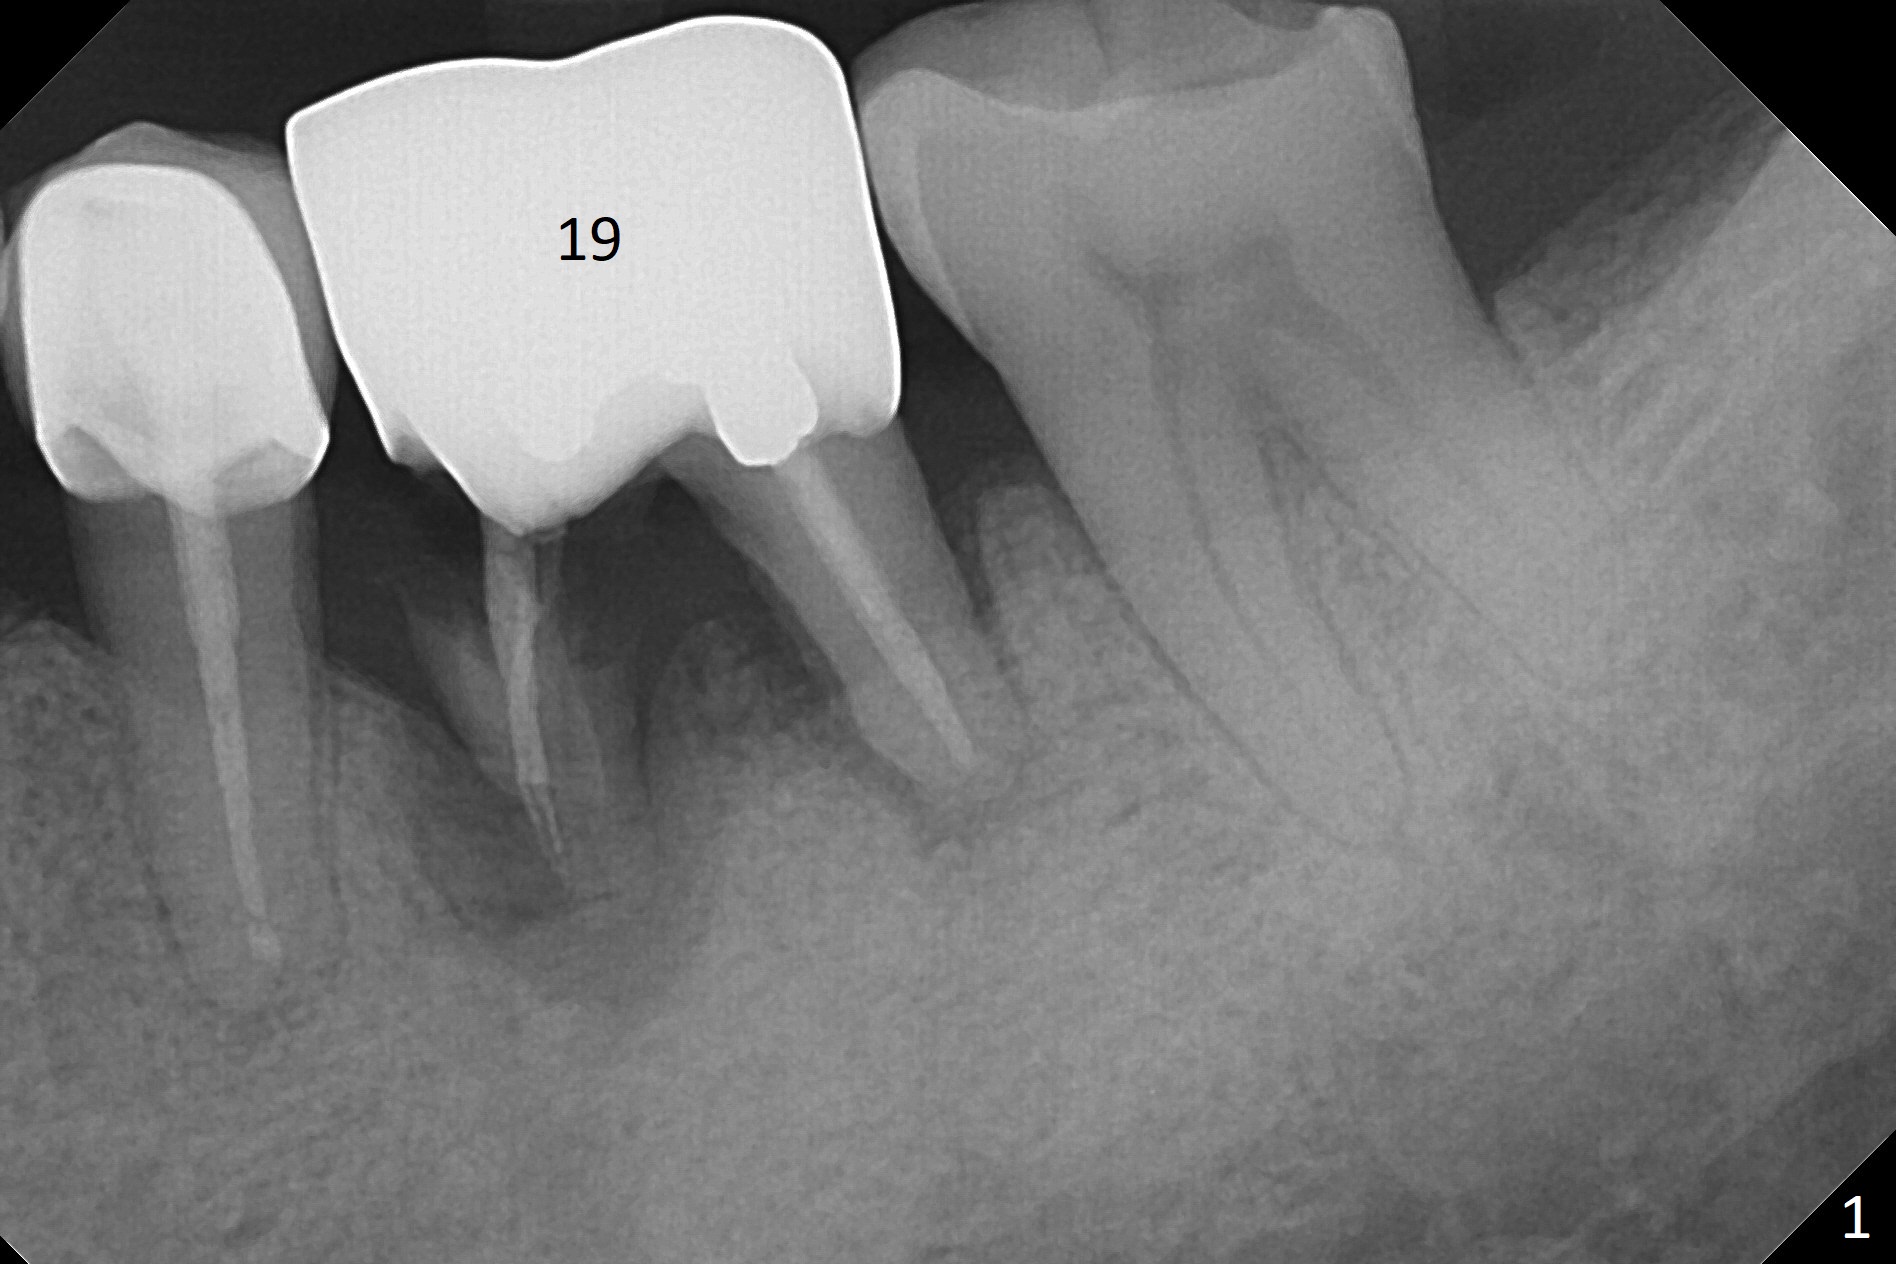

A 64-year-old man feels that the lower right 1st molar irritates the tongue. The mesial root fragment is sharp lingually (Fig.1). Initial osteotomy depth is 14 mm (gingival margin, Fig.2), as lingual as possible (Fig.3 CT taken on 01/21/2011).